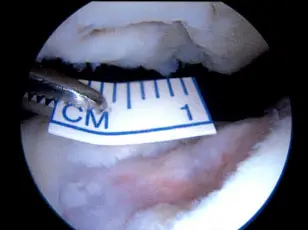

An MRI from the same patient's knee. The arrow points to the area on the patella (kneecap) where healthy, intact cartilage is missing.

An MRI from the same patient's knee. The arrow points to the area on the patella (kneecap) where healthy, intact cartilage is missing.How Can I Protect My Joint Cartilage?